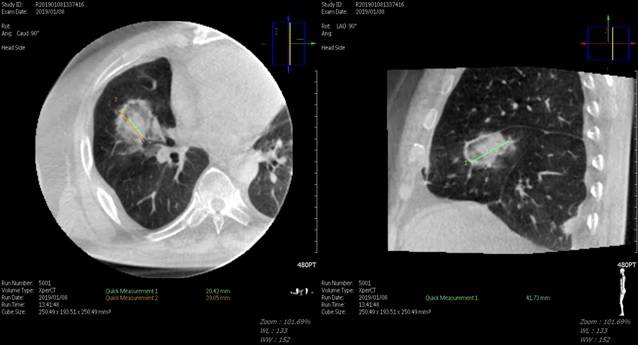

강북삼성병원 영상의학과 홍현표 교수 등 대장암팀이 대장암 폐 전이 환자를 치료할 때 생길 수 있는 부작용을 극복할 방안의 하나로 고주파 열 치료술을 진행해 그 효과를 확인했다. 폐암의 고주파 열 치료술은 CT, 초음파 등의 영상의학 장비 유도 하에 시술 기구를 안전한 경로로 폐 내부의 병변에 삽입시킨 후 열을 발생시켜 종양을 치료하는 기법이다. 국소 치료법 중 하나인 고주파 열 치료술은 수술이 어려운 간, 폐, 신장의 악성종양 수술의 대체 치료법으로 인정받고 있다.

연구팀은 다학제 진료로 결정된 폐전이 대장암 31명의 환자를 대상으로 시행된 폐 고주파 열 치료술 48회를 분석했다. 대부분 환자는 2박 3일 단기 입원을 해 국소마취를 한 후, 시술받았다. 3D 단층 영상을 재구성하는 Cone-beam CT로 표적을 정확히 타겟팅해 90%의 고주파술 성공률을 기록했고, 18% 정도에서 시술 후 기흉이 발생하는 합병증이 있었지만 임상적으로 큰 문제가 되는 경우는 없었다.